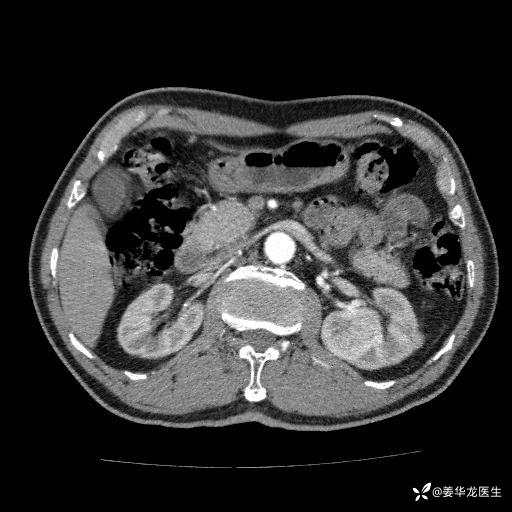

左肾中心型肾门部肿瘤39mm×34mm×36mm,右肾GFR25ml/min,部分切还是全切?

患者75岁老年男性,体重50kg,无高血压、肾病、糖尿病等基础病,检查发现左肾中心型肾门部肿瘤,右肾GFR只有25ml,无肉眼血尿,无镜下血尿。入院验血常规检查均正常,包括肾功能,肌酐102.7umol/L.

二、左肾肿瘤与左肾集合系、左肾动静脉关系密切,左肾部分切除术可行吗?成功率有多大?成功部分切后,肾功能还有多少?

四、左肾根治疗切除术后,透析的机率有多大?